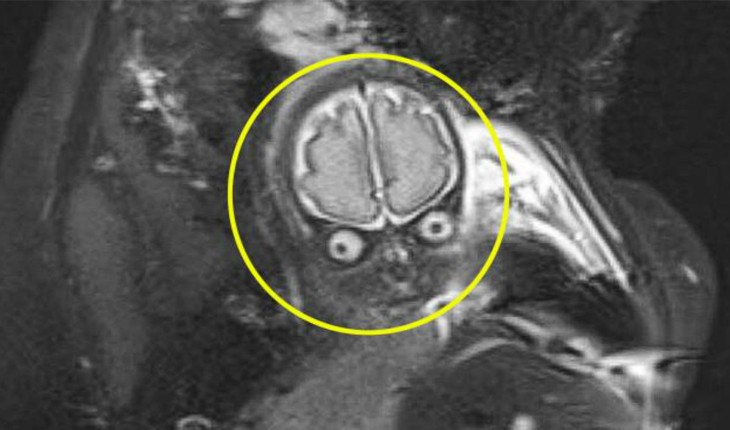

Os pais se assustaram ao ver as imagens do exame que foi feito com 30 semanas de gestação.